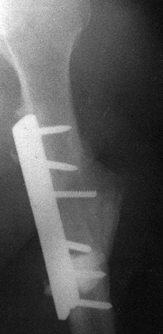

antibiotic-impregnated PMMA beads are encouraging, so the use of these

in selected cases seems appropriate (Fig. 133.1).

![]() |

Figure 133.1.

Anteroposterior roentgenograms of a 46-year-old man with chronic osteomyelitis. The patient was treated with debridement followed by insertion of aminoglycoside-impregnated methylmethacrylate beads and a local muscle flap. |